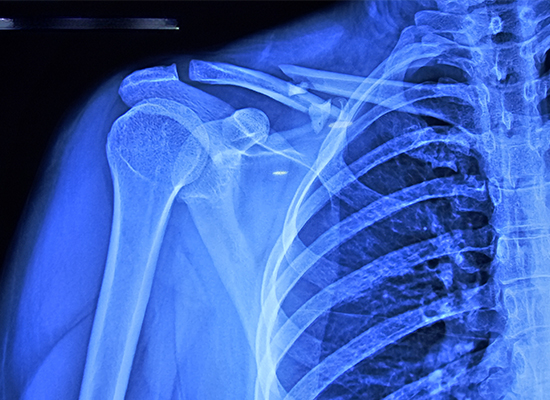

La paciente, una mujer de 34 años, sufrió una fractura de clavícula derecha clasificada como Allman tipo 1, es decir, se trataba de una fractura de la región media del eje diafisario. Este tipo de lesión muchas veces puede provocar complicaciones si no se trata correctamente. Después de examinar la condición de la paciente y revisar los resultados de sus imágenes, el Dr. Pedro recomendó un procedimiento de reducción abierta y fijación interna (ORIF) con una placa de bloqueo de clavícula en S.

La paciente de 34 años tenía una fractura diafisaria tipo I de Allman con múltiples fragmentos.

Debido a la naturaleza multifragmentada y desplazada de la fractura, la fijación conservadora no pudo lograr la alineación, por lo que se seleccionó ORIF.

La reducción abierta y fijación interna (RAFI) se realizó exponiendo los extremos de la fractura y fijándolos con una placa de bloqueo.